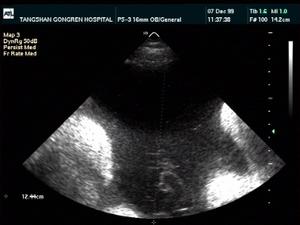

所谓羊水,是指怀孕时子宫羊膜腔内的液体。在整个怀孕过程中,它是维持胎儿生命所不可缺少的重要成分。在胎儿的不同发育阶段,羊水的来源也各不相同。羊水的多少都会在很大程度上影响胎儿的健康!